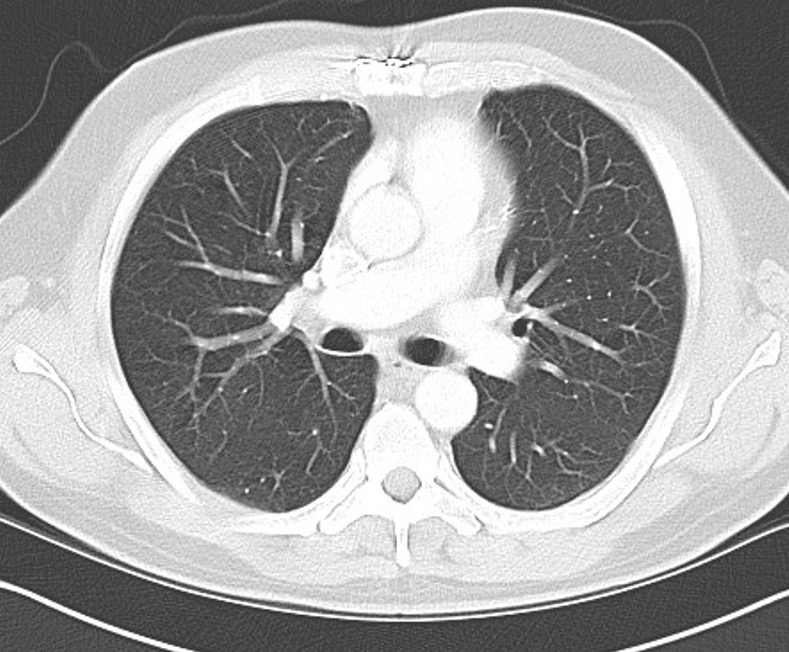

Staging

CXR, CT chest / abdomen

+/- bone scan, PET scan

Metastasis

- 10,000 sarcoma patients

- 25% will develop metastasis

- 50% metastasis: > 5 cm, deep to fascia, intermediate or high grade